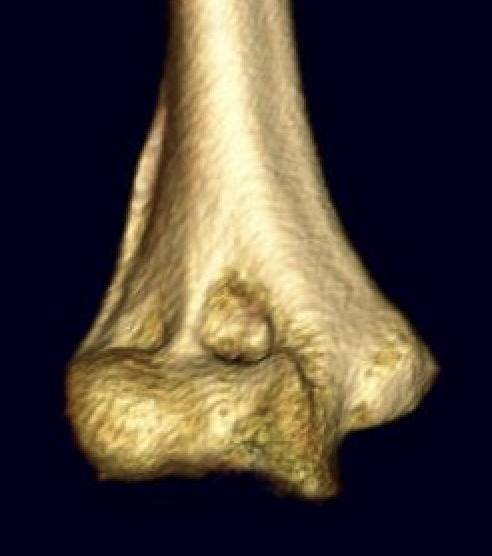

OTA / AO Classification

Type A: Extra-articular fracture

Type B: Partial articular fractures

Lateral condyle Medial condyle

Type C: Complete articular fractures

CT scan